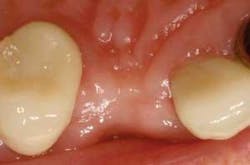

Figure 21 - Three-week postop view, facial closeup. Note the papilla development and soft-tissue architecture at three weeks postop. The implant-abutment-crown unit has integrated nicely.

Although only three-week postop results have been documented, already the technique holds promise. Papilla formation has occurred and the implant-crown unit is stable and healthy so far. The patient is taking more personal pride in her restoration and in her appearance, as evidenced by a dramatic improvement in plaque removal and overall oral hygiene observed at her three-week checkup.